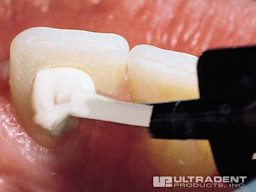

Step 1

Before starting the Opalescence Endo whitening procedure, a glass ionomer should be placed on the floor of the pulp chamber to seal the obturation from penetration of the hydrogen peroxide.

Place Opalescence Endo whitening gel into canal.

Step 2

Deliver mixed UltraTemp™ Regular temporary filling material directly to site through the Skini Syringe.